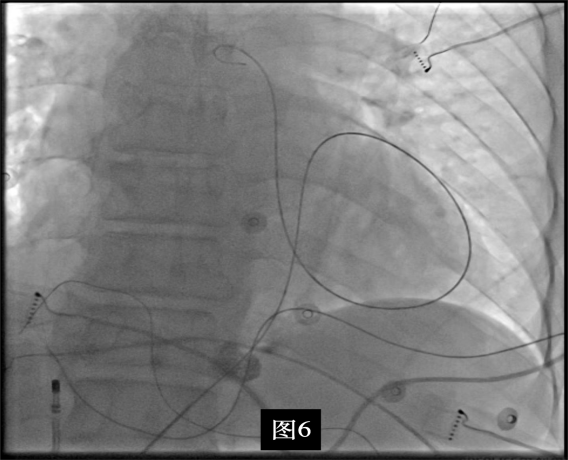

即穿刺股静脉,将消融大头送至冠状窦内,在GCV远端对应位置标测到最早点(图5绿色点)领先体表27ms,消融后早搏未能消失,周明礼评估起源点偏心外膜,能量依旧不能穿透损伤到起源点,内膜消融基本无效后,果断选择难度系数最为复杂的干性心包穿刺心外膜消融。在导丝的指引下,将消融大头送至心包层(图6),于外膜标测到靶点(图7黄色点)电位领先体表31ms,单极电位无r波且有顿挫,ssummit外膜离冠状动脉较近,比较危险,保证安全,进行了冠脉造影(图7),显示距离LAD和LCx有一定距离,相对安全,随即放电,2s室早消失,10s患者出现心率变慢,该区域走形迷走神经节,消融导致心率减慢,随后保证心率正常的情况下,消融够60s,随后观察半小时,早搏没有恢复,手术成功(图8)。经过不懈的努力,患者恢复了窦率,心脏功能也逐渐恢复正常,手术取得了圆满成功。